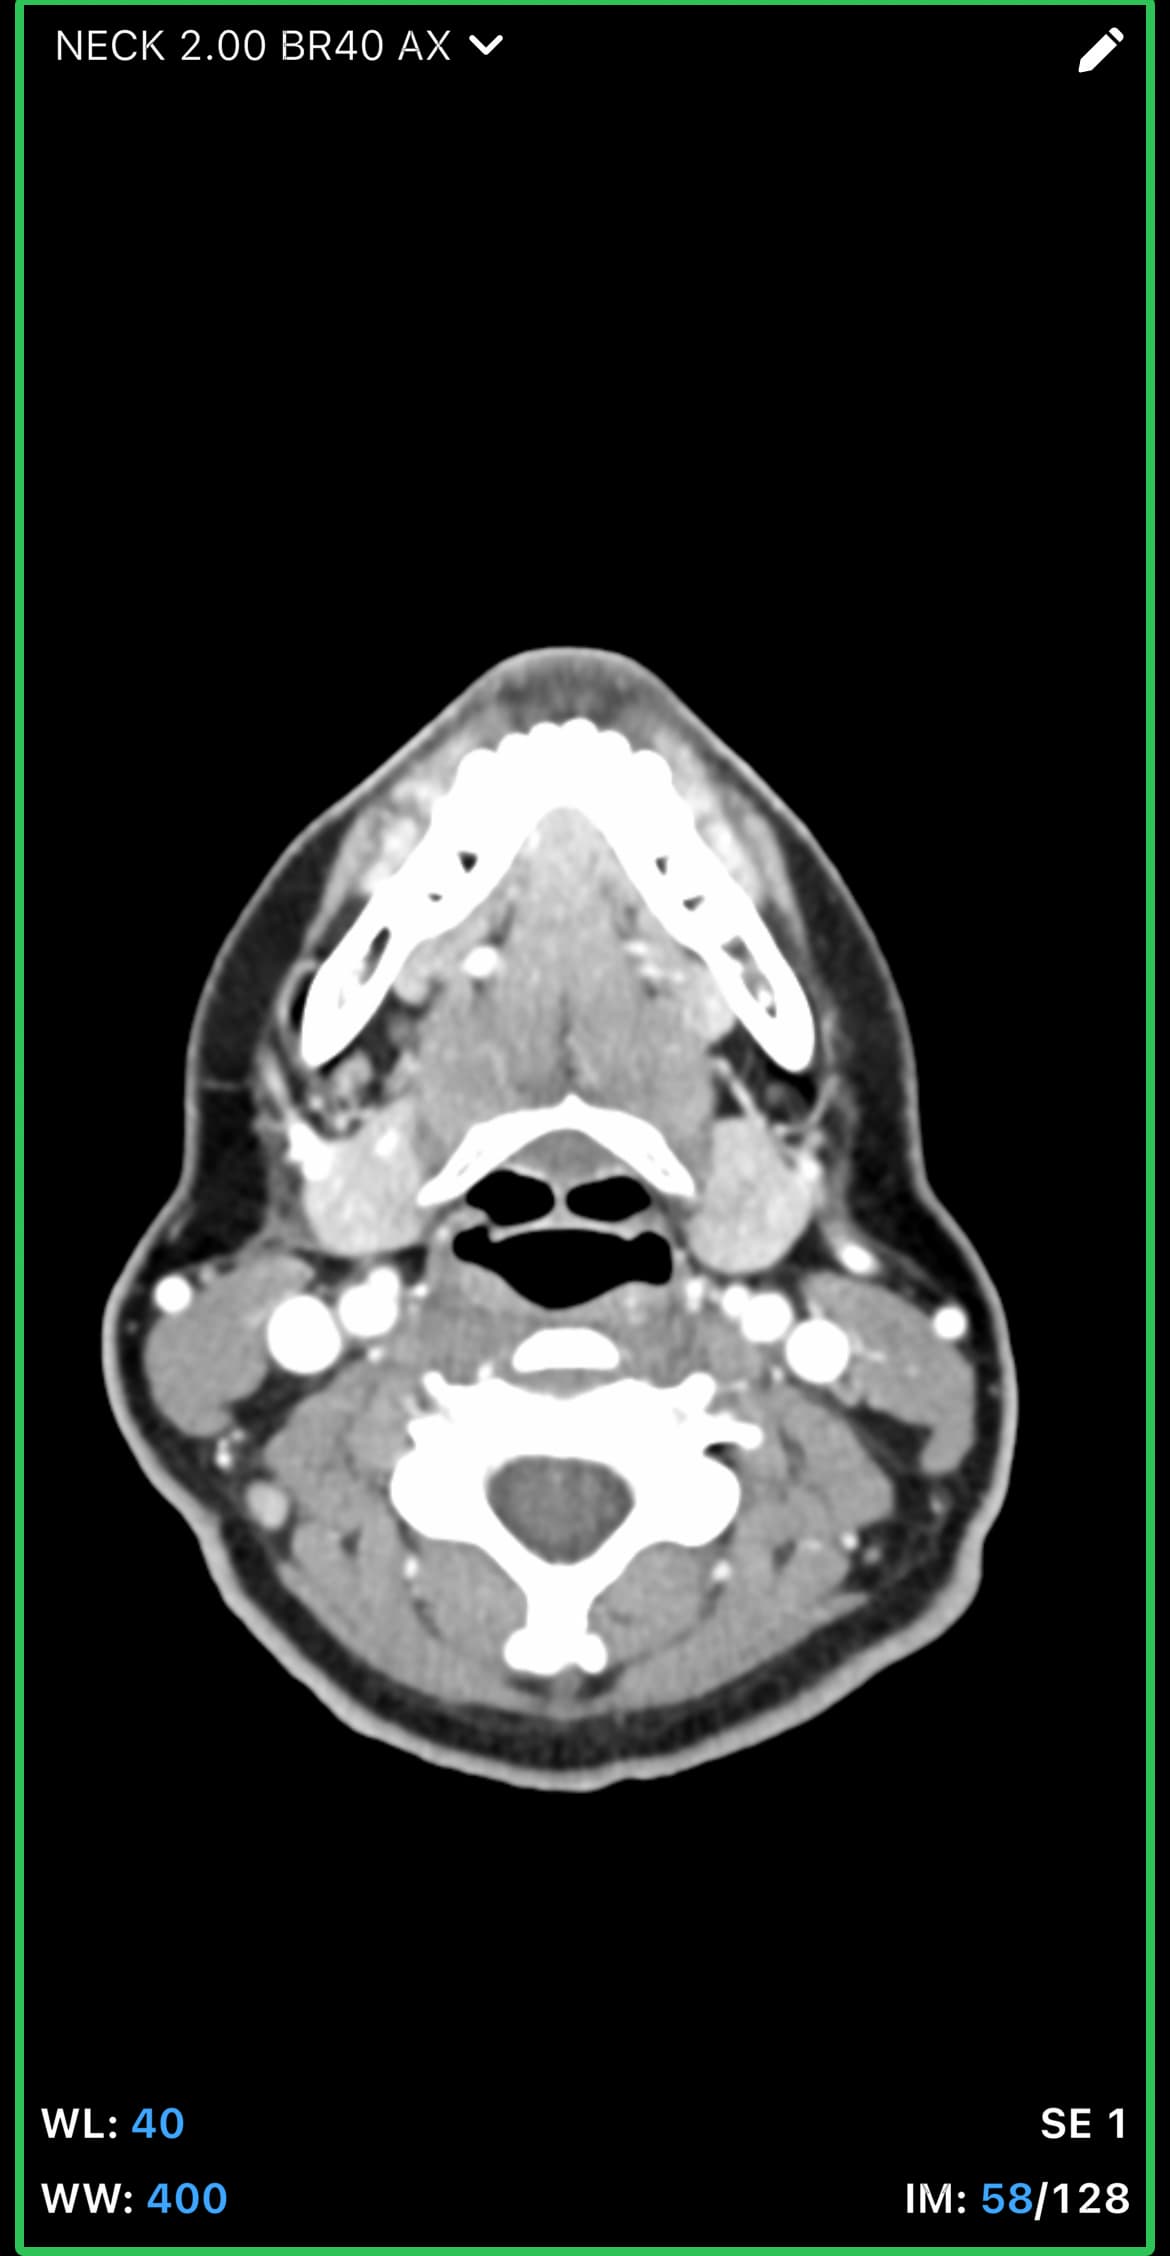

In your first & last pictures, you can see how close to your spine the greater horns of your hyoid are. Your whole hyoid looks like it’s been pushed back further in your neck than it should be possibly producing Hyoid Bone Syndrome (HBS).

@leo this is the closest one. Can you go back to your axial view and go to the very last slice that you can see the tips? I think you might be one or two frames off. I attached my imaging to help. Our hyoids might be at slightly different angles so it might not be a perfect comparison, but I think you can go up a slice or two to see the tips better. Basically follow the bone until it disappears then go back one frame to capture it.

Hi, I’m so sorry for the delay in replying to you, we had some family stuff come up and this got pushed to the back burner for awhile. I’ve gone back a few frames, am I getting closer? I can also send you the whole CT if that would make things easier. I’m sorry, I’m not good with technology. I appreciate you taking the time to respond! Since we last spoke, I’ve developed a lot of neurological symptoms and weird physical ones like dizziness, headaches, brain fog, weird throbbing in my neck and head, can this all be tied in with hyoid bone problems? Thank you so much for your time!

@leo - The new symptoms you’ve just mentioned i.e. dizziness, headaches, brain fog, weird throbbing in my neck and head are all those we see associated with internal jugular vein compression. From what I can see in the images you posted, it looks like you may have that going on, but I’ll let @TML give you more information.